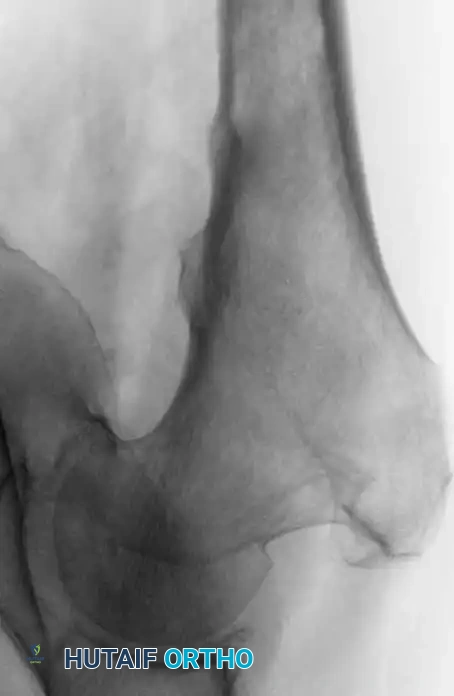

Fig. 22-24: (A, B) Anteroposterior and lateral radiographs of the proximal femur in an 82-year-old man with metastatic kidney cancer revealing multiple lytic lesions. Prophylactic fixation was canceled due to medical instability. (C) Radiograph several weeks later showing a completed pathological fracture. Surgery is now exponentially more difficult, and the patient has suffered severe morbidity.